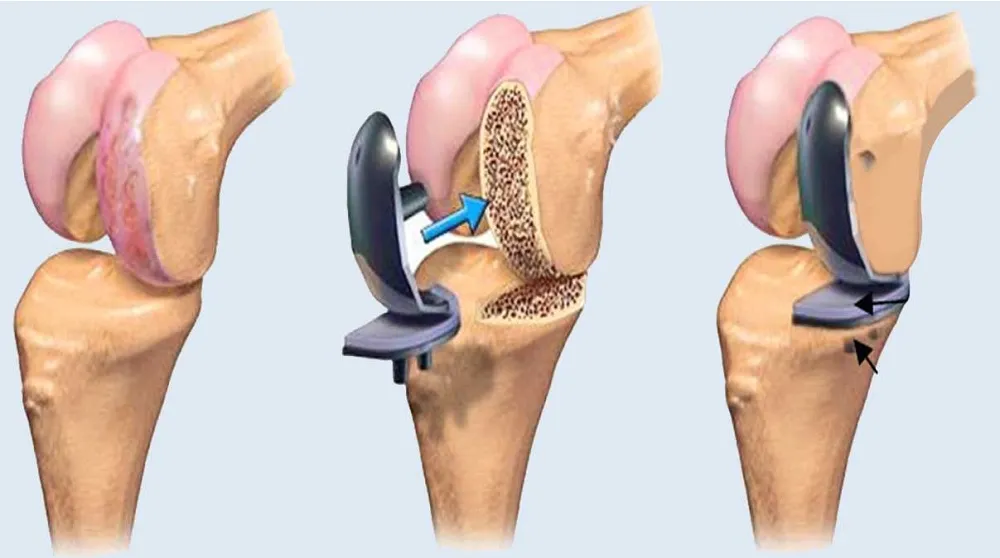

Right Knee Replacement (Total Knee Arthroplasty)